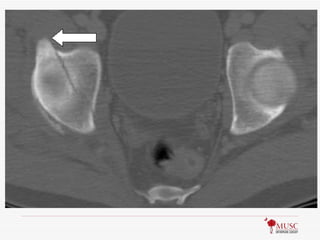

Question #: 160A patient sustains a fracture of the acetabulum. An axial CT scan is shown in Figure 160. What structure takes origin from the region depicted by the arrow? 1- Pectineus 2- Sartorius 3- Iliopectineal fascia 4- Direct (straight) head of the rectus femoris 5- Indirect (reflected) head of the rectus femoris

Preferred Response: 4Rectus femoris has 2 heads: Direct/straight takes origin from AIIS, Indirect/reflected takes origin from groove on the upper brim of the acetabulum Femoral nerve (L2,3,4) Arterial supply: ascending branch of lateral femoral circumflex Pectineus  origin from superior surface of pubis; innervated by femoral & obturator (L2,3,4); acts to adduct thigh Sartorius  origin from ASIS; innervated by femoral (L2,3); inserts into pes anserinus